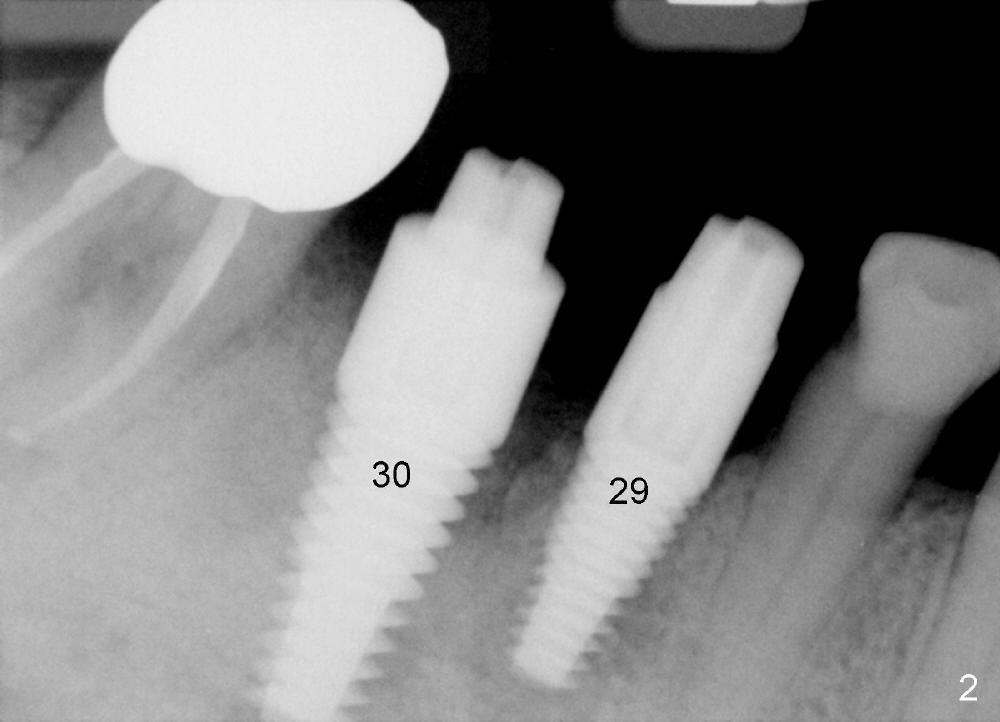

One month after implant placement at the sites of #29,30, the former is found loose (Fig.1,2). It is placed higher than #30. Three weeks later, PA is retaken to confirm that there is space apical to the implant at #29 (Fig.3 double arrows) and that there is distance from the mental loop (yellow dashed line). After infiltration anesthesia, the implant is torqued down initially (compare Fig.4,5) and more (Fig.6,7). To prevent re-loosening, the two implants are splinted (Fig.8).

There are several possible reasons for #29 loosening. Implants are placed almost on the right and left sides at the same time. The patient is a bruxer. Abutments placed immediately are used to hold perio dressing in place. After perio dressing is dislodged, the patient may chew with the abutments. There is distal wall defect associated with #29 socket when the tooth is extracted and socket preservation is done.